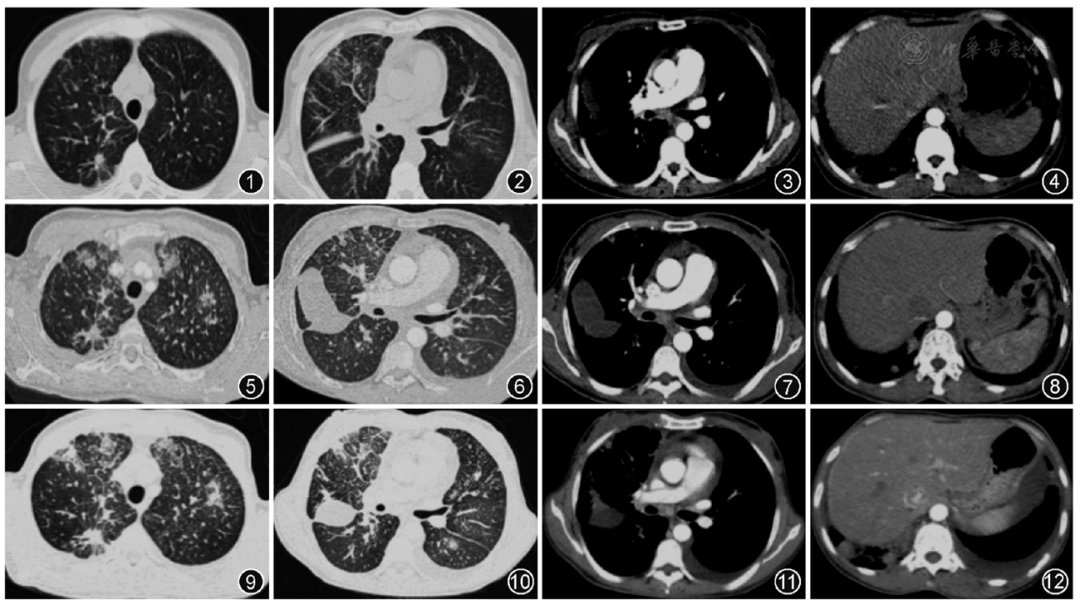

临床病例理讨论以肺栓塞起病的双肺多发病变

图片尺寸1080x605